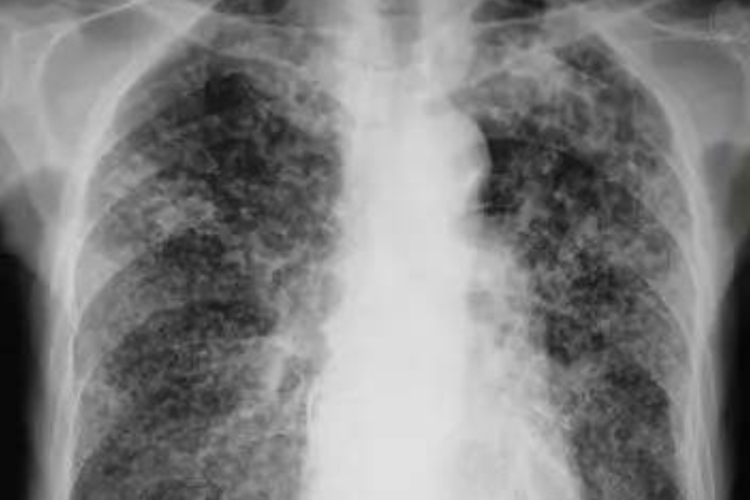

亚急性血行播散型肺结核表现为双肺上、中野粟粒状或较粟粒更大的小结节影,其大小不一、密度不等分布不均,即“三不均匀”。肺尖部及锁骨下病灶可为硬结、钙化及纤维化,其余病灶呈增殖或渗出性改变。